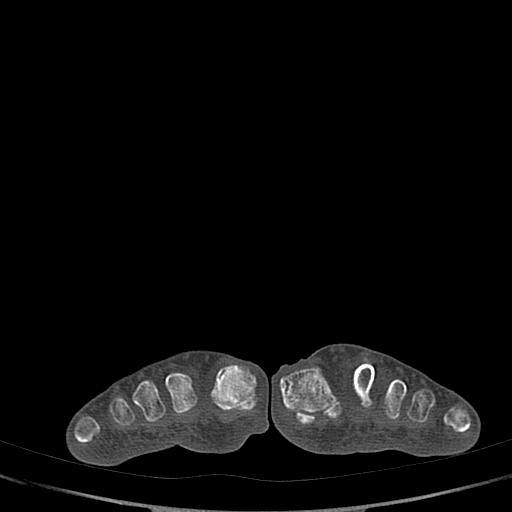

标题: CT13415:M72Y,跖趾关节病变,请会诊 [打印本页]

标题: CT13415:M72Y,跖趾关节病变,请会诊

男72岁左侧跖趾关节肿痛15年,查压痛。